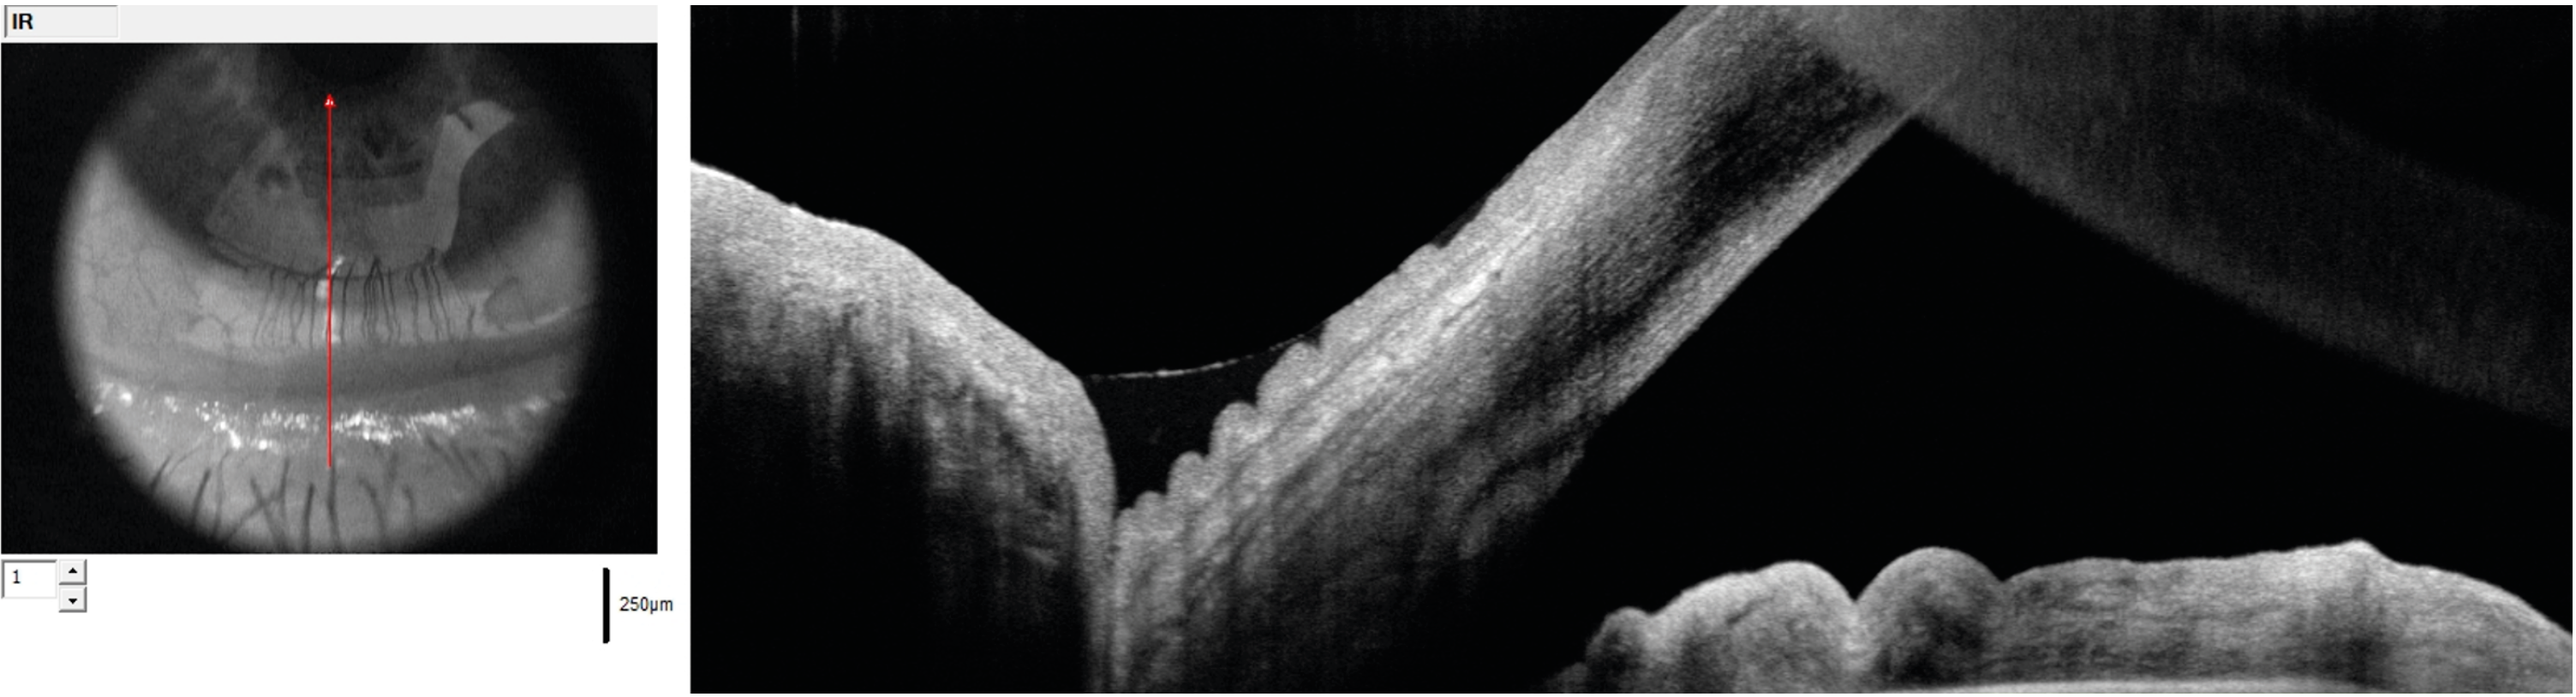

Figure 2. Le trabéculum juxtacanaliculaire dans la pince lors d’une sclérectomie profonde. C’est ce trabéculum qui offre 80 % de la résistance à l’écoulement de l’humeur aqueuse par la voie trabéculaire.